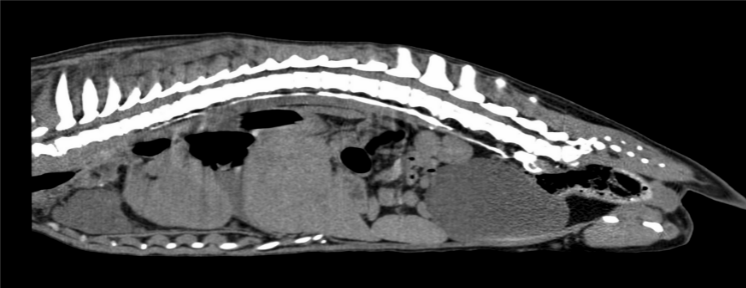

・CT 検査:CT 検査を実施する目的としては

・腫瘍や血栓など二次性乳び胸の原因となるものがないかの確認

・リンパ管造影を実施して胸管の走行や乳びが漏れている位置の確認

・手術計画の立案があり手術を実施する上で重要な検査となります。

リンパ管は通常の血管造影だと造影されないため、このように肉球に造影剤を入れてマッサージをすることでリンパ管造影を行います。